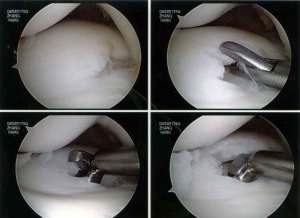

As the patient was very young, I decided to reshape the discoid lateral meniscus and repair the torn parts back to the capsule. This is a reconstruction of the discoid lateral meniscus. I feel that this is a much better option than cutting the lateral meniscus away. Removing almost the entire lateral meniscus will definitely lead to a lot of pain and disability in this young lady.

Firstly the discoid portion of the lateral meniscus was removed arthroscopically as shown:

Next, the torn part of the meniscus was repaired to the capsule using a combination of all-inside and inside-out meniscus repair technique.

The final reconstructed discoid lateral meniscus looked like this: